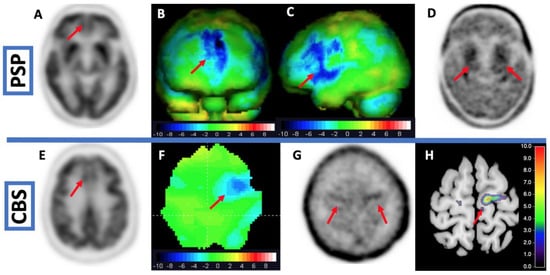

- Brendel, M.; Barthel, H.; van Eimeren, T.; Marek, K.; Beyer, L.; Song, M.; Palleis, C.; Gehmeyr, M.; Fietzek, U.; Respondek, G.; et al. Assessment of 18F-PI-2620 as a Biomarker in Progressive Supranuclear Palsy. JAMA Neurol. 2020, 77, 1408–1419. [Google Scholar] [CrossRef] [PubMed]

- Palleis, C.; Brendel, M.; Finze, A.; Weidinger, E.; Bötzel, K.; Danek, A.; Beyer, L.; Nitschmann, A.; Kern, M.; Biechele, G.; et al. Cortical [18F]PI-2620 Binding Differentiates Corticobasal Syndrome Subtypes. Mov. Disord. 2021, 36, 2104–2115. [Google Scholar] [CrossRef]

- Beyer, L.; Nitschmann, A.; Barthel, H.; van Eimeren, T.; Unterrainer, M.; Sauerbeck, J.; Marek, K.; Song, M.; Palleis, C.; Respondek, G.; et al. Early-Phase [18F]PI-2620 Tau-PET Imaging as a Surrogate Marker of Neuronal Injury. Eur. J. Nucl. Med. Mol. Imaging 2020, 47, 2911–2922. [Google Scholar] [CrossRef]